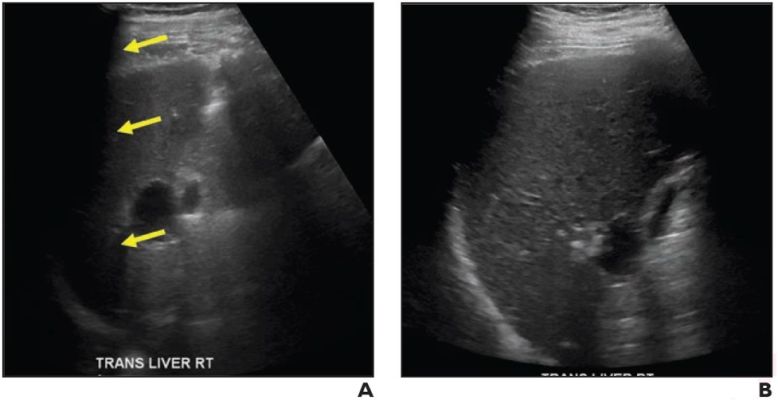

69-Year-Old Man With Chronic Hepatitis B. (A) Transverse gray-scale ultrasound image shows inability to visualize portion of liver. Examination received visualization score C. (B) Transverse gray-scale ultrasound image from examination performed 9 months later shows improved visualization of liver. Examination received visualization score A.

Noting any decision should consider the number of previous examinations with score C, “only 42% of patients with visualization score C on surveillances examination have score C on follow-up examination,” wrote corresponding author Aya Kamaya, M.D., from the department of radiology at Stanford University School of Medicine in California.

Ultimately, the probability of repeat visualization score C on a subsequent examination increased with an increasing number of preceding examinations with score C. Frequency of score C was 42%, 67%, and 80% after 1, 2, and 3 consecutive preceding examinations with score C.